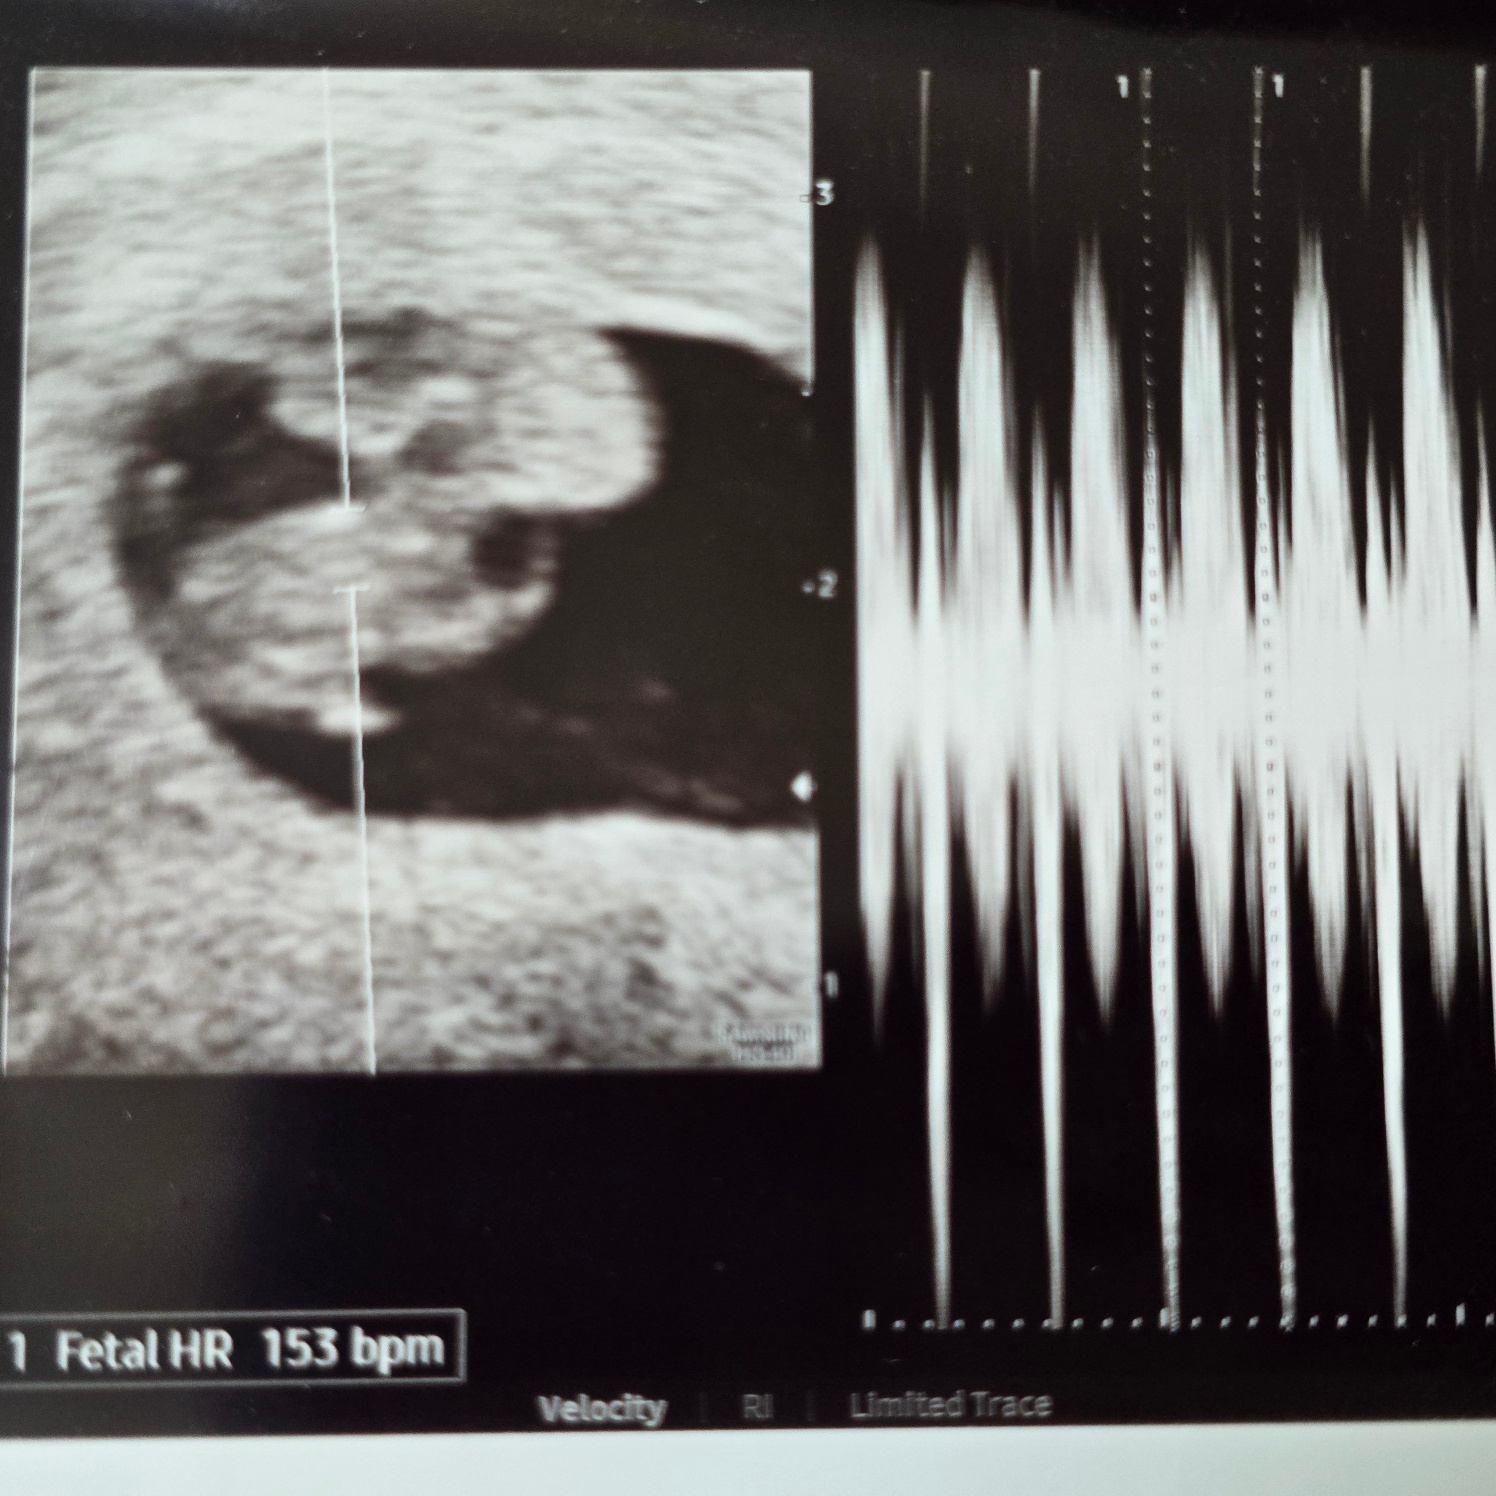

커져있는 아기집과 난황!!

그리고 아기 심장소리까지 들었다!!!!

아기 3일 전에 봤는데 딱 3일만큼 잘 커있고 아기 심장도 쿵쾅쿵쾅 잘 뛰니까 걱정 말라고 해주셨다.. 휴..

7주 2일엔 난황이랑 비슷한 크기였는데 7주 6일엔 난황보다 커졌다!!!

우리 뚝딱이 잘 크고 있구나~!!!

뚝딱이 크기는 7주 2일 크기로 4일 작게 꾸준히 잘 크고 있었다!!ㅎㅎ